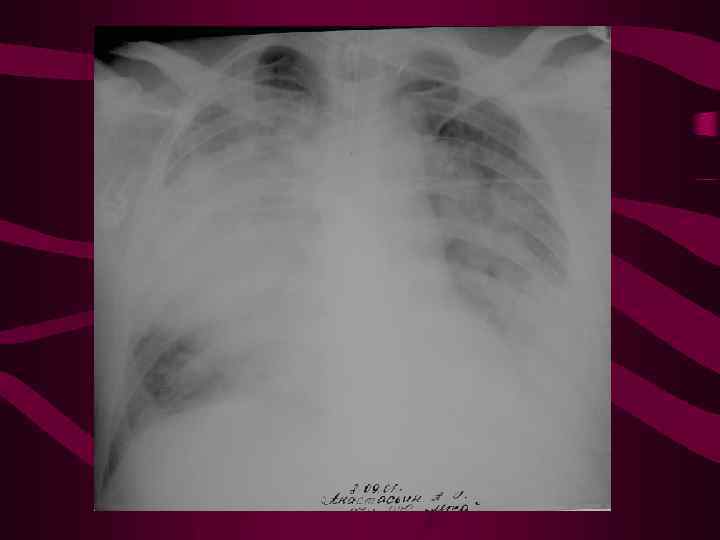

Альвеолярный отек характеризуется появлением участков безвоздушной легочной ткани различной формы и размеров, от небольших инфильтратов с нечеткими контурами до уплотнения значительной части легкого локализация безвоздушных участков легочной ткани вне зависимости от долевого и сегментарного строения легкого Характерно:

Альвеолярный отек характеризуется появлением участков безвоздушной легочной ткани различной формы и размеров, от небольших инфильтратов с нечеткими контурами до уплотнения значительной части легкого локализация безвоздушных участков легочной ткани вне зависимости от долевого и сегментарного строения легкого Характерно:

Типичные рентгенологические признаки (кардиогенного) альвеолярного отека: инфильтратоподобных теней средней интенсивности в центральных задних отделах легких с двух сторон перераспределение легочного кровотока (цефализация) значительное расширение, уплотнение и нечеткость очертания корней легких линии Керли, перибронхиальные муфты, плевральный выпот быстрая динамика как при прогрессировании, так и при обратном развитии процесса (часы - 1 -2 суток) расширение размеров сердца и сосудистой ножки

Типичные рентгенологические признаки (кардиогенного) альвеолярного отека: инфильтратоподобных теней средней интенсивности в центральных задних отделах легких с двух сторон перераспределение легочного кровотока (цефализация) значительное расширение, уплотнение и нечеткость очертания корней легких линии Керли, перибронхиальные муфты, плевральный выпот быстрая динамика как при прогрессировании, так и при обратном развитии процесса (часы - 1 -2 суток) расширение размеров сердца и сосудистой ножки